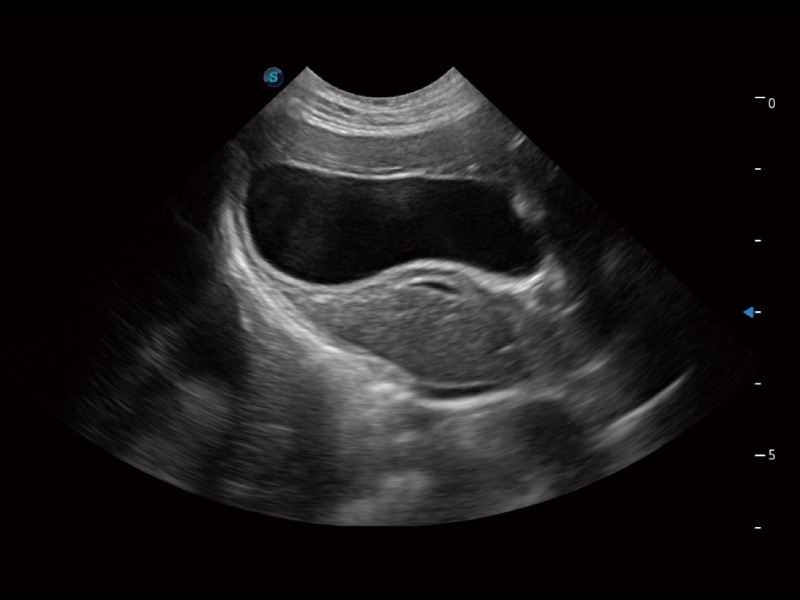

一鍵自動識別膀胱壁及自動測量膀胱容積,不受膀胱形狀和大小的限制,幫助醫(yī)生快速精準(zhǔn)獲得測量的數(shù)據(jù)。

ProPet 70專為動物醫(yī)生設(shè)計,對不同的動物體型和生理結(jié)構(gòu)作出了針對性的優(yōu)化。通過動物影像專用軟件,可滿足個性化的應(yīng)用需求,幫助動物醫(yī)生獲得更精確的診斷數(shù)據(jù)。

為精細(xì)結(jié)構(gòu)及組織邊緣提供高清晰度的圖像和更大的成像視野。幫助減輕醫(yī)生的用眼疲勞,快速精準(zhǔn)獲得測量的數(shù)據(jù)。